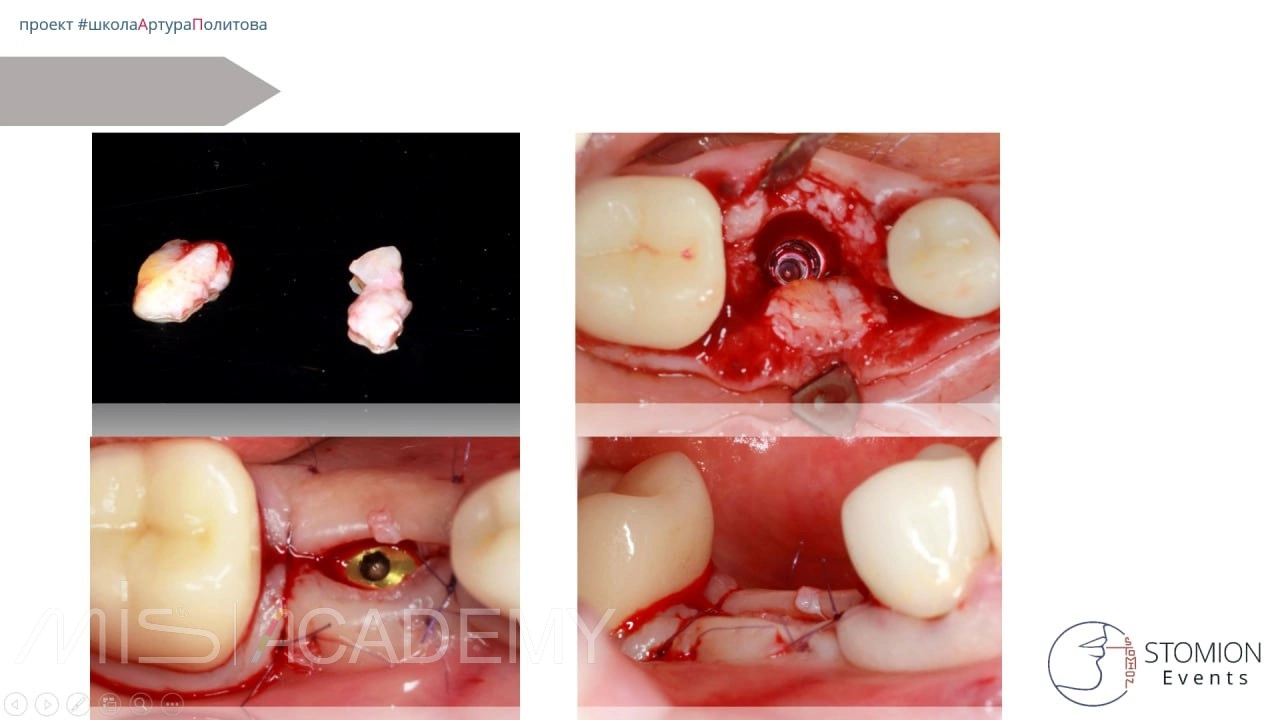

Клинический случай с использованием широкого коннекта 5,7 мм на MIS C1.

1. Проведено удаление зуба 4.6 с формированием и стабилизацией кровяного сгустка.

2. Через 3 месяца установлен имплантат MIS C1 размером 3,75 × 11,5 мм.

3. Установлен коннект шириной 5,7 мм, высотой 2 мм.

4. Через 3 дня изготовлена и зафиксирована временная коронка.